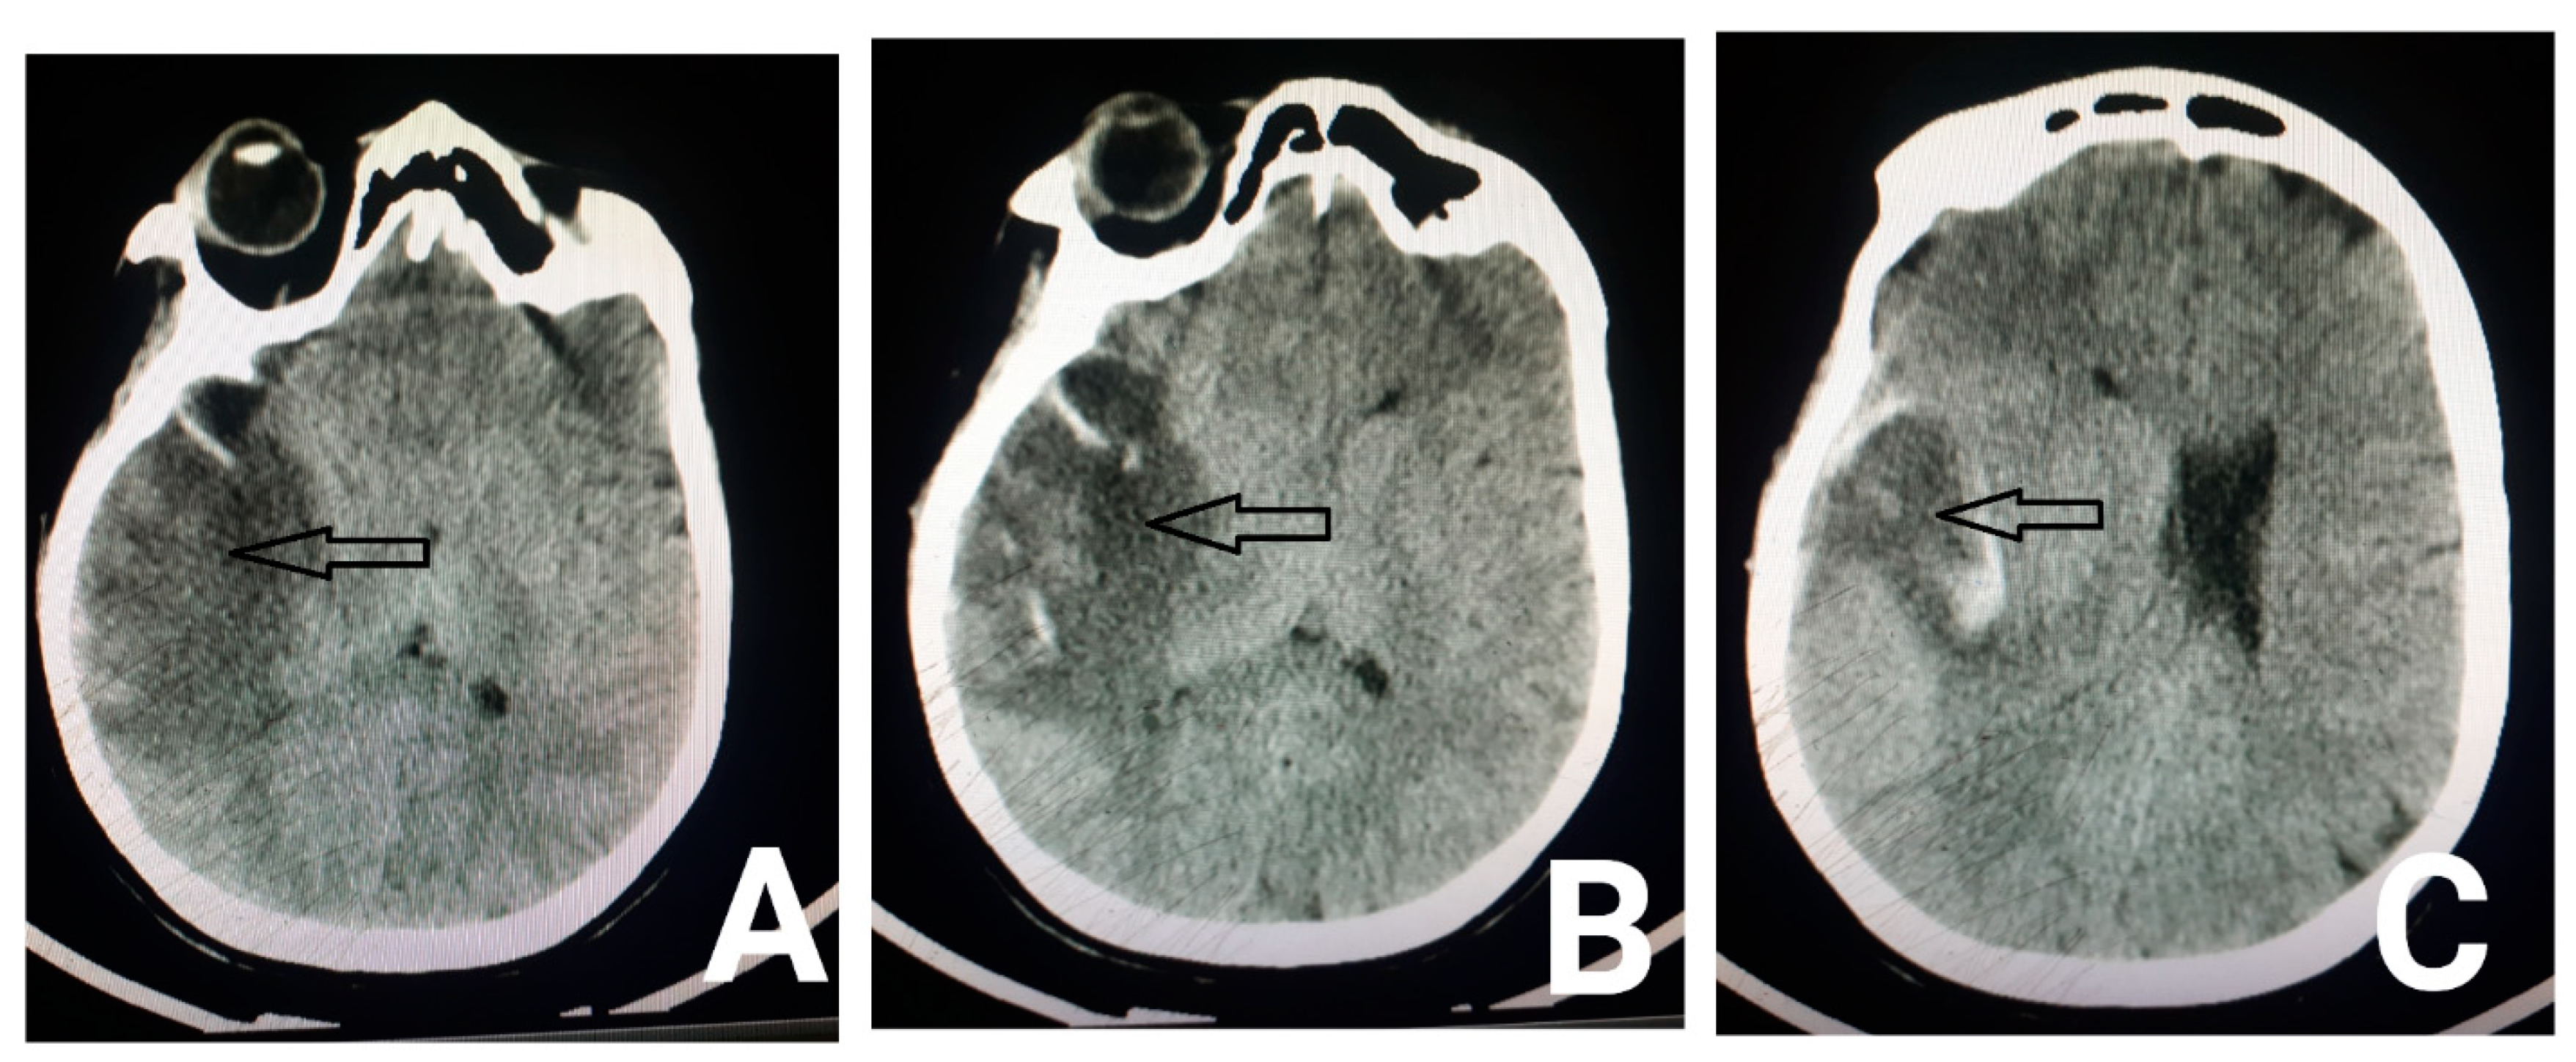

2. Case Presentation